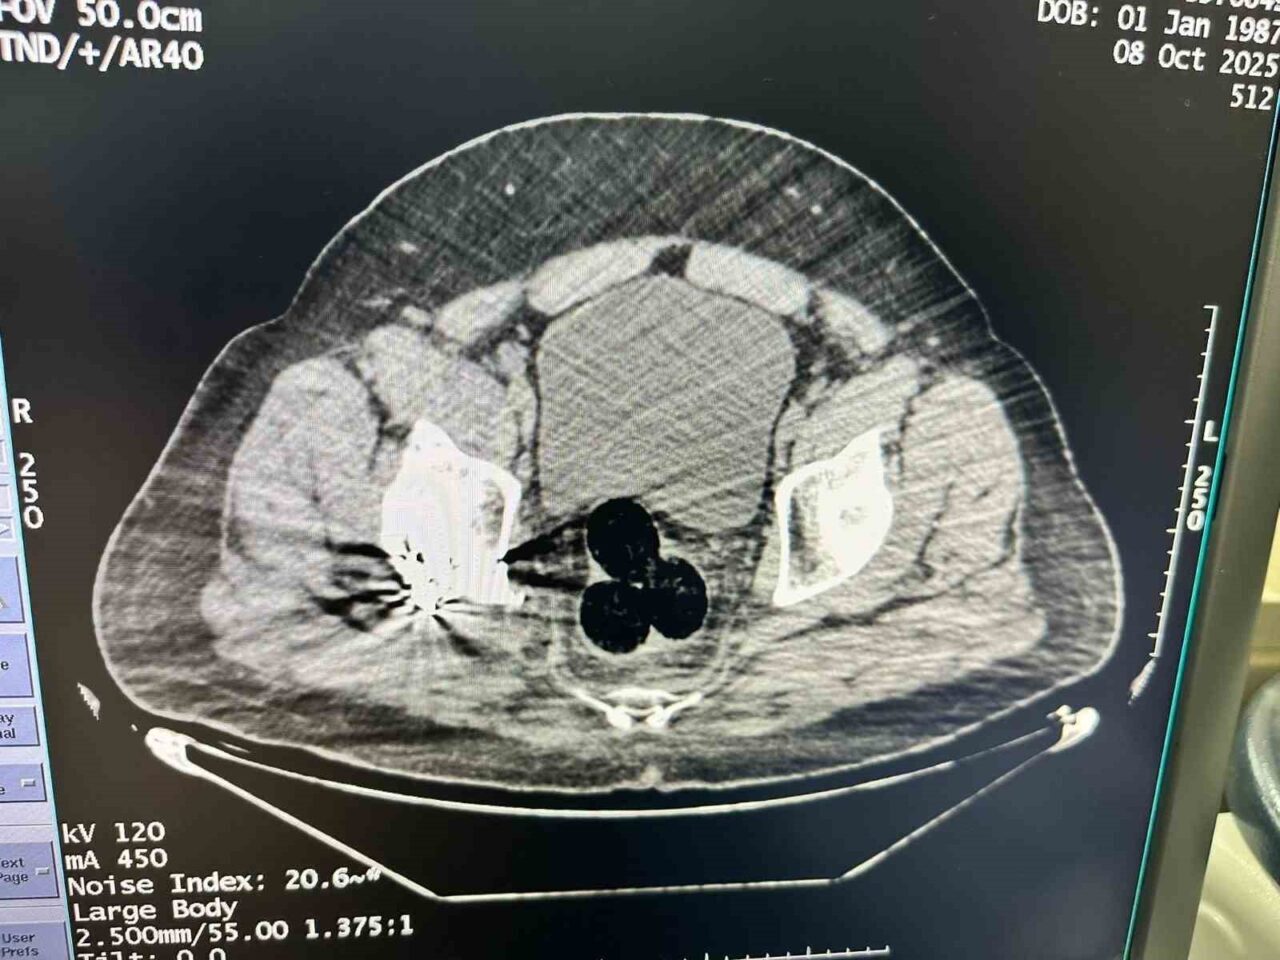

Alınan bilgilere göre, Iğdır İl Emniyet Müdürlüğü Narkotik Suçlarla Mücadele Şube Müdürlüğü, İran’dan yasa dışı yollarla ülkeye giriş yapan bir şahsı şüphelenerek takibe aldı. Gözaltına alınan bu kişi, uyuşturucu madde bulguları tespit edilmesi amacıyla hastaneye sevk edildi. Muayenede, şüphelinin makat bölgelerinde üç adet yabancı cisim belirlendi.

Cerrahi Müdahale ile Uyuşturucu Ele Geçirildi